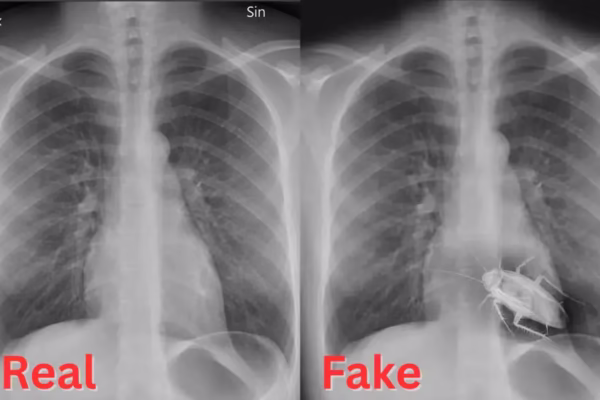

A Cockroach That Never Crawled-And One That Actually Did

A bizarre photo claiming to show a live cockroach inside a chest X-ray from Kolhapur has been buzzing across social…